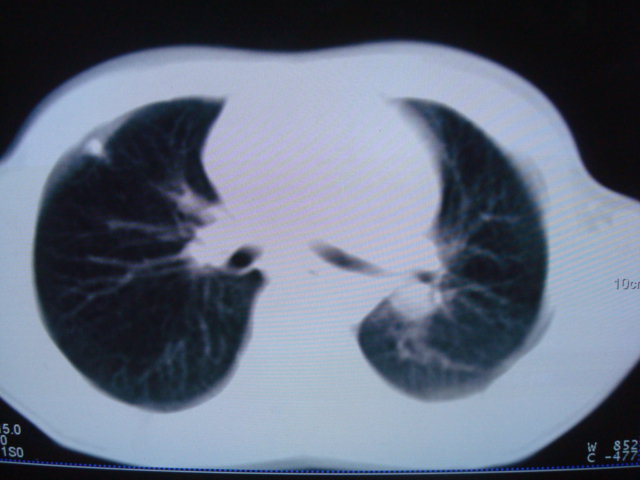

标题: PED0869:男,10岁,肺内多发结节+胸水

男,10岁,左胸痛,发热轻,血象高。后到省级权威医院治疗,病情明显好转,结果几天后公布。老机器,图像质量差,见谅。